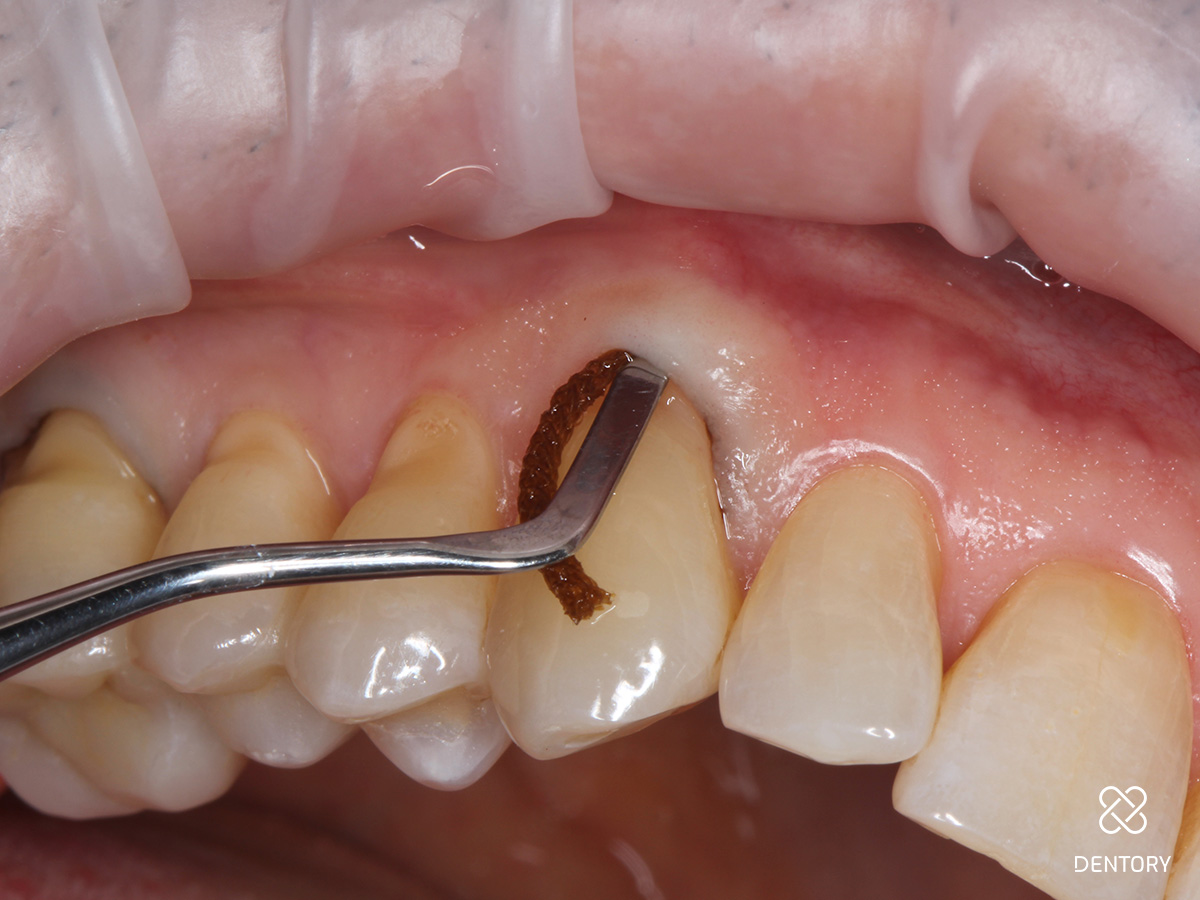

Abbildung 7

Entfernung der Bondingreste: Nach sicherem Durchhärten werden die eventuell überstehenden Füllungsränder oder Überreste des Bondings mit einer EVA-Feile vorsichtig entfernt - der Faden wird hierbei belassen, somit wird das Gewebe weniger verletzt. Mit einer Sonde wird getestet, ob alle Ränder einen glatten Übergang aufweisen. Achtung: Politur der Füllung mit Komposit-Polierern (Kelche eignen sich besonders gut).